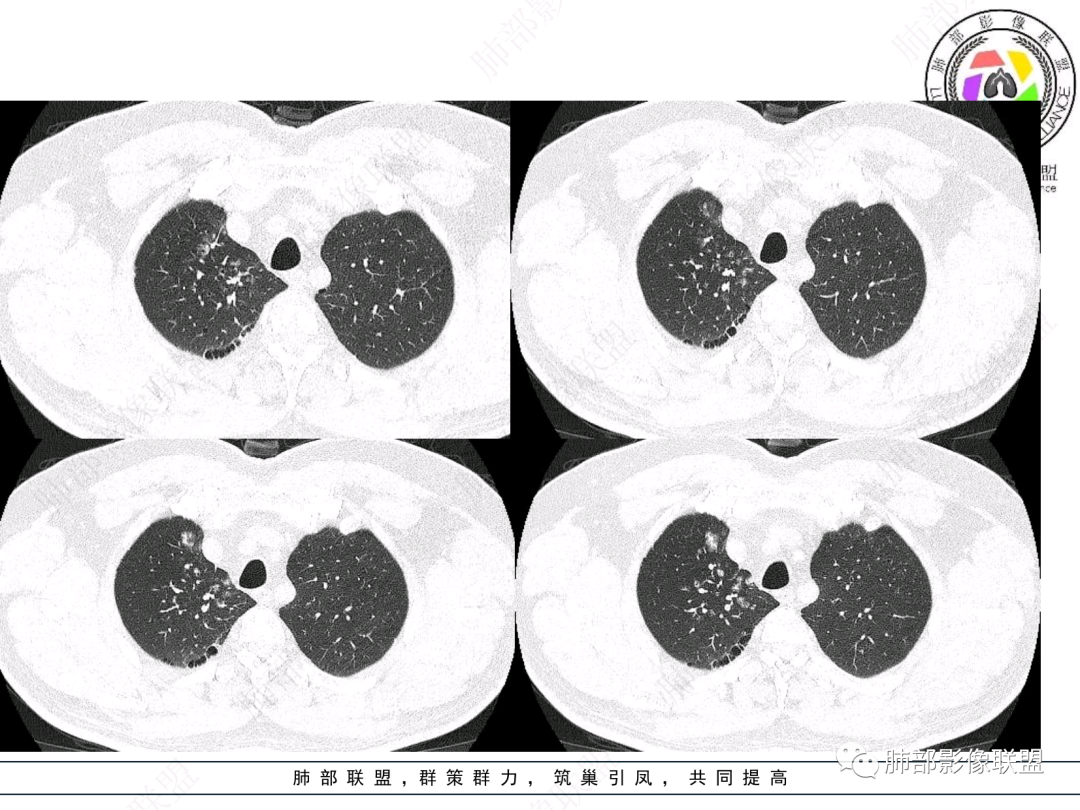

右肺上叶支气管截断,内见软组织密度结节,支气管管壁破坏,病变侵及管外,增强强化明显。右肺上叶沿气管血管束多发斑片影,考虑恶性性病变并阻塞性炎症,鳞癌,神经内分泌肿瘤。

右肺门病灶,支气管腔内堵塞,见有多处低密度影,支气管镜下凹凸不平,直观下不像鳞癌,恶性肯定的,考虑腺样囊性癌可能。

右肺主支气管-上叶支气管腔内结节伴钙化,轻度强化,考虑类癌,鉴别错构瘤与结核。

老年男性,咳嗽咳痰,右肺门增大,右主支气管开口见高密度影,密度不均匀,轻度强化,右肺上叶见多发腺泡结节,支气管管壁增厚,近端粘液栓,支气管镜检查见新生物,考虑鳞癌,鉴别结核。

右主支气管及肺门不规则软组织结节,点状钙化,不均匀强化,气管壁破坏,上叶支气管阻塞,分支粘液栓,血管束增粗,沿支气管分布多发结节,考虑鳞癌合并阻塞性炎症,鉴别结核。

右气管腔内结节,右肺门肿物,有钙化,右侧肺内多发气腔结节,散在,左肺部分支气管壁增厚,首先分析气管内结节,多考虑1鳞癌,形态规则,边缘光滑,宽基底,不太支持,远端阻塞性炎症不典型,2类癌,冰山一角和冰山分离了,不太支持3结核,多为支气管壁广泛增厚钙化,形成结节少,但是肺门肿块有钙化,可作为结核支持点,4黏痰,不像。其他不太懂了,肺内多发磨玻璃结节,并可见支气管手指状扩张,综合分析影像,考虑感染性病变,结核?有没有这样子的气管曲霉呢?向老师们学习。

老年男性,右肺门主支气管腔内软组织肿块影,密度不均,有钙化,右上叶支气管腔部分阻塞,强化较明显,右肺上叶远端散在斑片状高密度影,相应支气管壁厚,树丫状腺泡结节,常规首先考虑结核,鉴别类癌。

右主支气管占位,累及全层,中度强化,远端管壁增厚,似乎花花草草,恶或者低度恶性。疾病谱:鳞(必须首先考虑 概率),腺样囊腺癌(位置 年龄符合 似乎强化也符合),类癌(强化不太支持),良性,结核(妖)。综合考虑腺样囊腺癌。

男性,52岁,右侧主支气管腔内外占位伴点状钙化,病灶大部分位于腔外,右肺上叶散在结节影,气管腔内病灶,动脉期中度强化,静脉期强化减低,首先考虑气管腔内类癌可能,鉴别鳞癌,肺内病变倾向感染性病变;再有气管结核伴肺内播散。

男,52。间断咳嗽、咳痰2周,加重3天。胸部CT:右主、右上叶支气管多发软组织影,跳跃不连续,内可见小环状高密度,点状钙化,管壁破坏,上叶支气管堵塞,远端分支粘液栓,可见小支气管管壁增厚、管腔狭窄,沿支气管分布多发结节,无大片炎症不张。考虑:TB?NTM?鉴别Ca并阻塞性炎症。

这个病例比较好,我们的观察点在哪?这是右上叶支气管病变,需要了解:腔内、壁、腔外、远端,腔内有软组织密度影,近端膨隆。